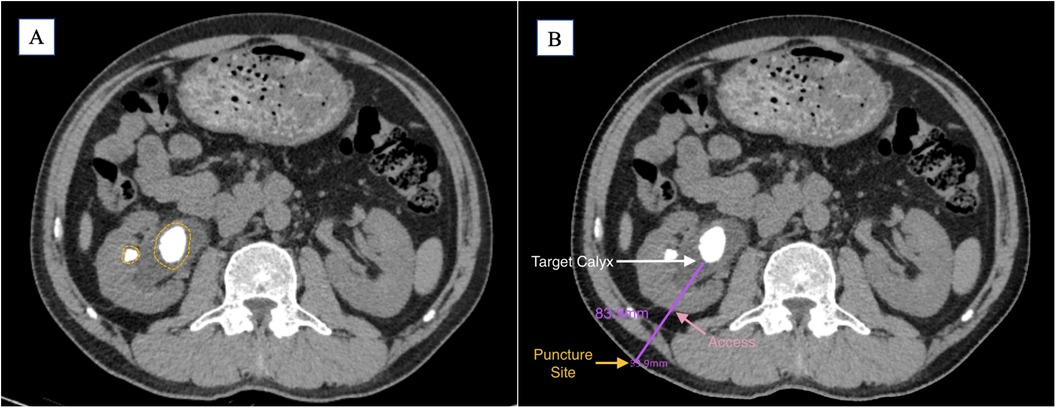

The puncture trajectory should target the central axis of the target calyx, adhering to the shortest and safest path through the renal cortex. While a perpendicular skin entry is ideal, angulation may be required to optimize precision and minimize tissue traversal (Figure 1).

Figure 1. (A) Preoperative CT imaging shows the main stone located in the renal pelvis, with a small stone visible in the mid-anterior calyx (yellow circle). (B) Based on the preoperative findings, the target calyx is selected (white arrow); the shortest perpendicular path to the skin is indicated (pink arrow); the puncture point is marked (yellow arrow); the estimated puncture tract length is 83.9 mm (purple line).